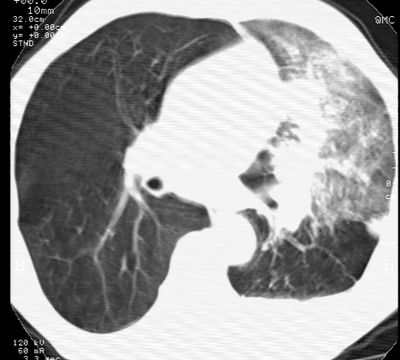

标题: CT24000:M65,胸痛,胸闷月余,既往慢支,肺气肿,肺心病 [打印本页]

标题: CT24000:M65,胸痛,胸闷月余,既往慢支,肺气肿,肺心病

左肺门肿块,相应支气管闭塞,左肺上叶、舌叶大片及散在高密度影,部分呈不张改变,两肺纹粗乱,左侧胸腔积液。考虑左侧中央型肺癌伴阻塞性改变。

左肺门见巨大软组织肿块影,直径约--,境界清,左上肺叶支气管变窄,左上肺舌叶见大片状密实影,余肺纹理增多、紊乱、纤细、部分网格状,两肺透亮度增高,纵隔内见增大多发淋巴结影,心影略左偏,左侧少量胸腔积液。

左侧中央型肺癌伴左上肺舌叶不张、纵隔淋巴结转移,左侧少量胸腔积液。